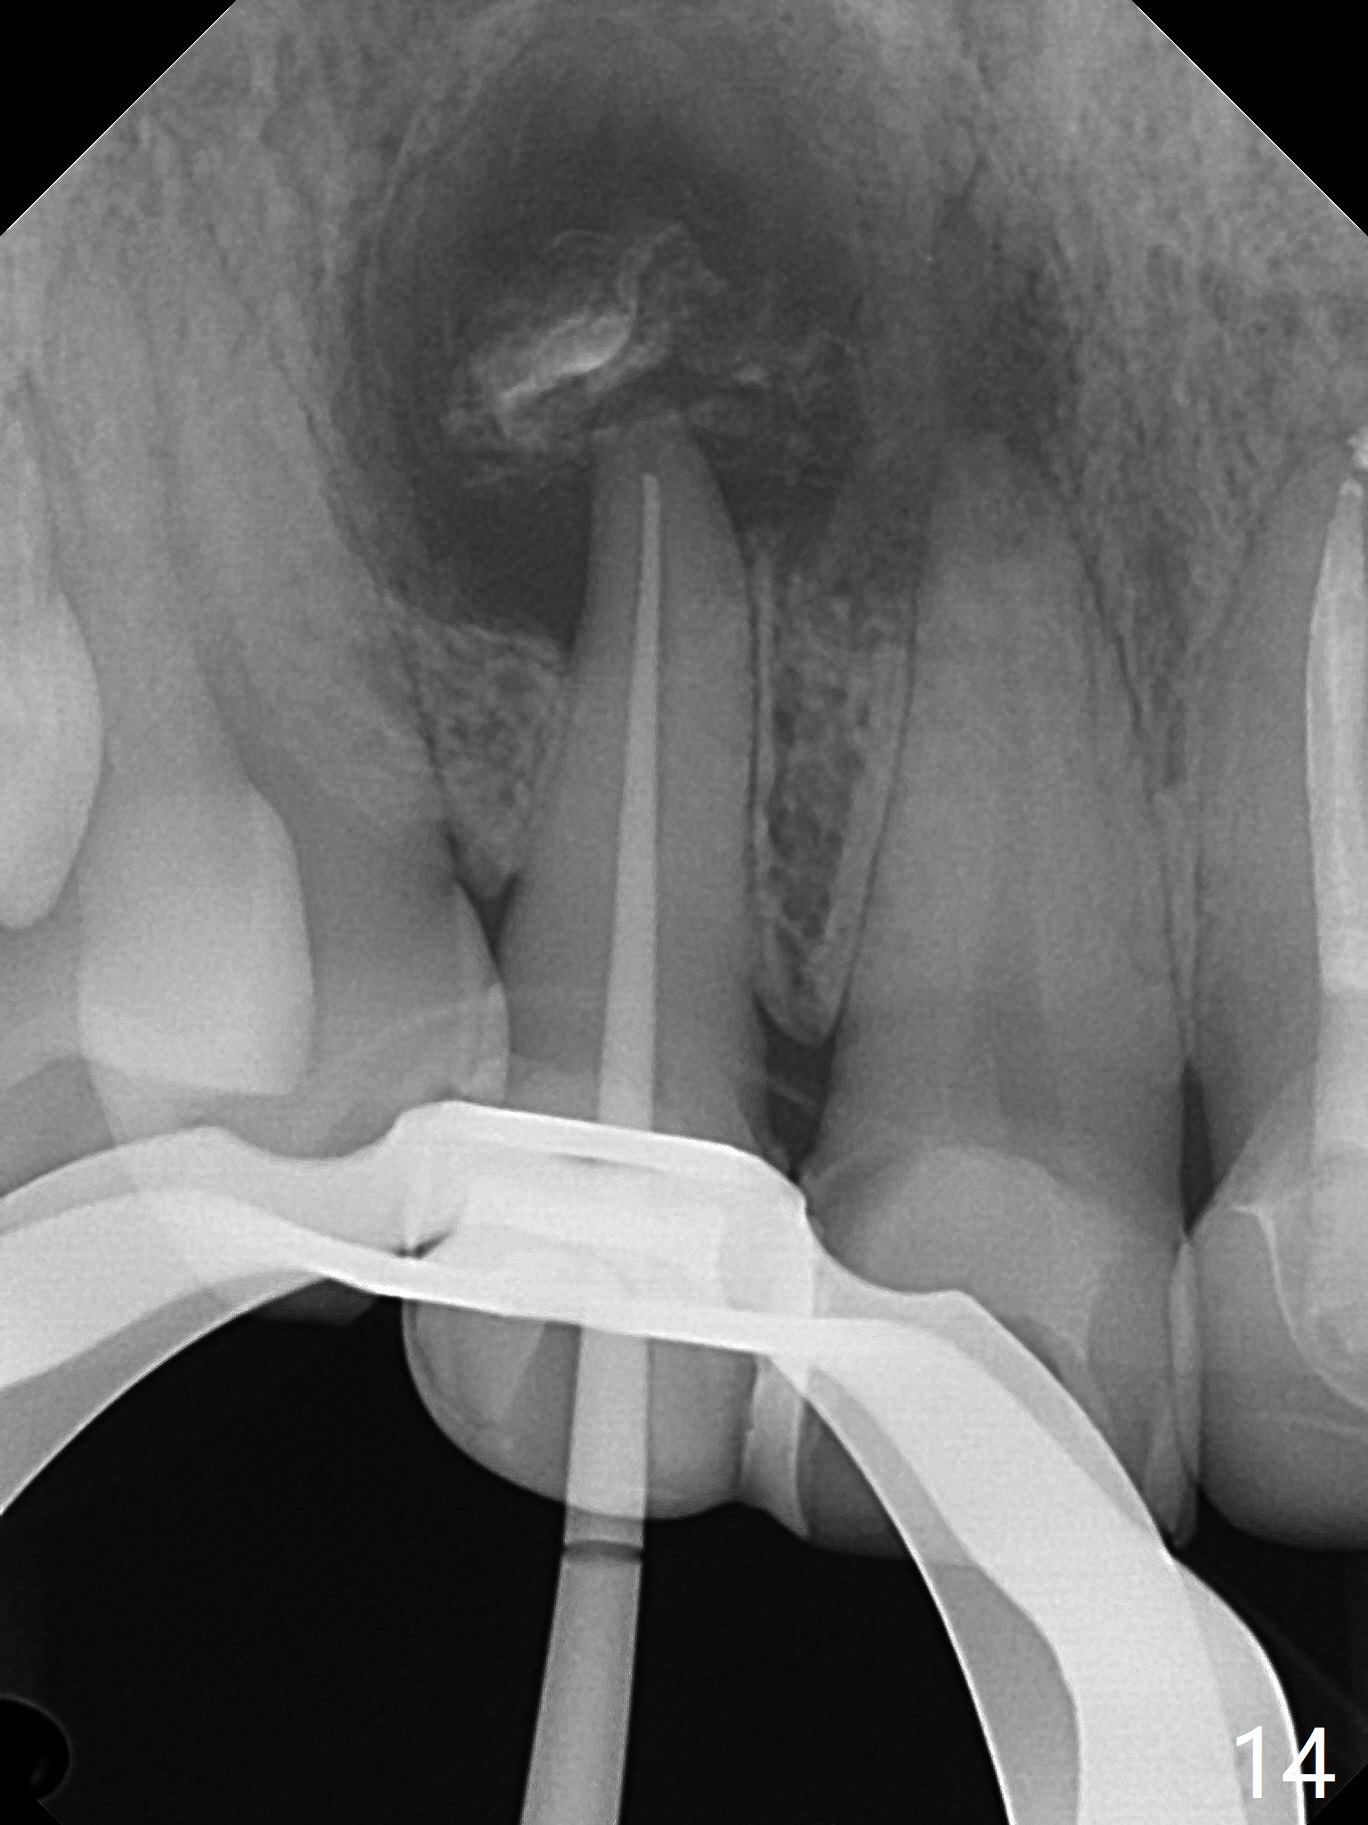

A 47-year-old woman (dental phobic) presented to clinic 9.5 years ago with periapical radiolucency (PARL) at #7 and 9 (Fig.1). RCT was done at #9 because of fistula and symptom 6 months later (Fig.2). While PARL increases at #7 without symptom, that at #9 disappears 8.5 years postop. Three months later, the patient returns for #7 RCT because of the abscesses (Fig.4 *) and pain. Intraop PA is taken with a 30/.06 rotary file in the canal with 19 mm working length (Fig.5). After use of #15 hand file for 20 mm, Ca(OH)2 paste is applied in the canal. When the rubber dam is removed, the abscesses enlarge (Fig.6), which may be related to sodium hypochlorite leakage. A dental explorer is used to try to find a bony opening to the large PARL without success (Fig.7). A postop PA reveals the leakage of Ca(OH)2 paste (Fig.8). Review of the preop PA (Fig.3,9) and intraop PAs (Fig.5,10) shows possible apical resorption and open apical foramen, which is the basis for the paste leakage (Fig.8,11). Careful analysis (with magnification and room light off) of pre- and intra-op PAs should be able to avoid use of #15 hand file out of apical constriction and the complication. The abscess has receded 1 month later (Fig.12). The paste has been resorbed 1 month later (Fig.13). A 30/.06 Gutta Percha is inserted at 18.5 mm (Fig.14 vs. 30/.06 file at 19 mm, 15 file at 20 mm last visit). Fig.15 is the final PA after closure of the access with composite (Fig.15).